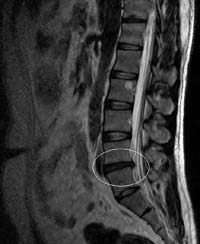

Межпозвонковая грыжа

Межпозвоночная грыжа (межпозвонковая грыжа, грыжа межпозвоночного диска) — это смещение пульпозного ядра межпозвоночного диска с разрывом фиброзного кольца. Наиболее часто встречаются грыжи межпозвонковых дисков пояснично-крестцового отдела позвоночника (150 случаев на 100 000 населения в год), значительно реже наблюдаются грыжи в шейном отделе позвоночника, наиболее редки — в грудном отделе. Хотя грыжи относительно редко требуют хирургического вмешательства, тем не менее в США ежегодно проводится более 200 тысяч, а Германии 20 тысяч вмешательств. В 48 % случаев грыжи локализуются на уровне L5-S1 пояснично-крестцового отдела, в 46 % случаев — на уровне L4-L5, остальные 6 % на других уровнях или на нескольких уровнях пояснично-крестцового отдела.

Методом выбора диагностики грыж межпозвонковых дисков в настоящее время является магнитно-резонансная томография (МРТ). При необходимости проводится неинвазивная МР-миелография или инвазивная КТ-миелография.